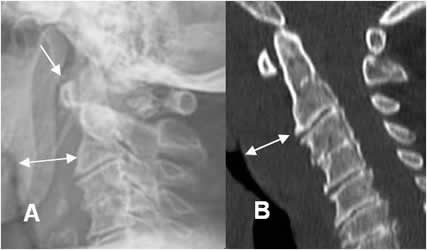

Fig 4A. Espacios normales.

TAC reconstrucción sagital. Espacio prevertebral sobre C3 y retroesofágico, a nivel de C6.

Fig 4B. Desalineación.

Rx lateral. Anterolistesis post-traumática, con interrupción en las líneas vertebral anterior y posterior. Igualmente hay aumento del espacio retrofaringeo.